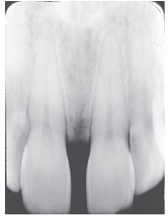

What is the problem with this Foreshorteningl X-ray?

Excessive vertical angulation, Short teeth with blunted roots

How would you resolve this Foreshortening X-ray?

Move PID